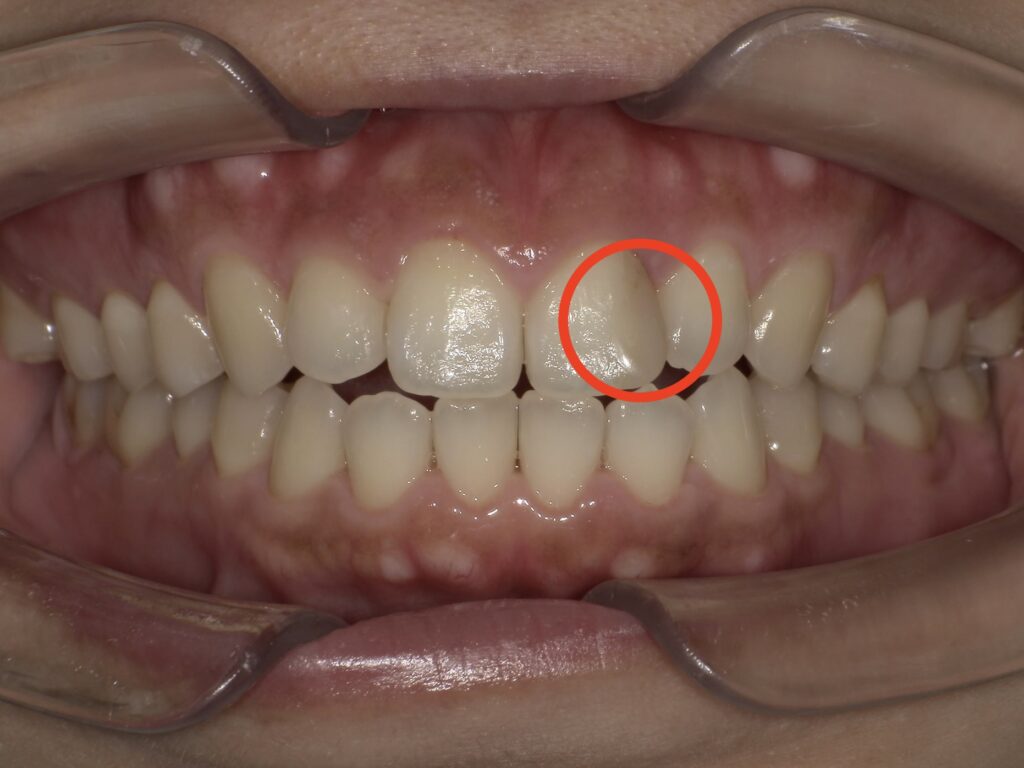

ホワイトニング前の、歯の色を見てください。

少し黄色い感じに見えますね。

あとは、前歯の詰め物の色が気になる部分を治します。

歯と歯の間に虫歯があったのでしょう。

当時の治療でされている詰め物(CR:コンポジットレジン)が変色しています。